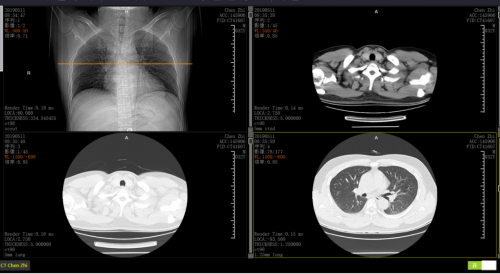

低剂量螺旋CT比胸片敏感4-10倍

肺部结节一般要大到1.5-2cm,才可能在胸片中显现出来,而且有些特殊的结节在影像上仅仅表现为斑片状或磨砂玻璃影,通过胸片检查根本发现不了。而直径约0.5cm的肺部肿瘤都可通过低螺旋剂量CT清晰检测成像,其肺癌诊出率约为胸片的10倍。

辐射少,能够减少88%的射线

常规胸部CT扫描的辐射剂量为3-27mSv,为胸片的10-100倍,而低剂量螺旋CT肺部扫描辐射剂量仅为常规CT的26%。